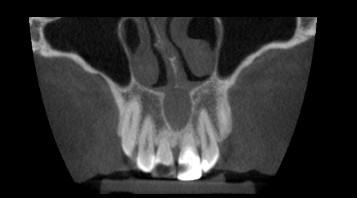

Streszczenie: Artykuł omawia przypadek torbieli otworu przysiecznego, która stanowi rzadką, trzecią co do częstości występowania, torbiel kości szczęk w postaci jasnego fragmentu skóry o konkretnym kształcie. Przeanalizowano przebieg leczenia ww. torbieli, a także przedstawiono istotne dla jej rozwoju możliwe czynniki zapalne, pozostałe torbiele występujące w tym obrębie, możliwe objawy oraz leczenie opisywanej zmiany. Rekonwalescencja zmiany może stanowić spore ryzyko ze względu np. na silne ukrwienie obszaru przy występowaniu małopłytkowości krwi (zaburzenie hemostazy).

Summary: The article discusses the case of an incisive canal cyst, which is a rare, third in the frequency of occurrence, cyst of the jaw bone in the form of a light skin fragment of a specific shape. The authors have presented the course of treatment of the above-mentioned cysts as well as possible inflammatory factors crucial for its development, other cysts present in this area, possible symptoms and treatment of the described lesion. The [...]